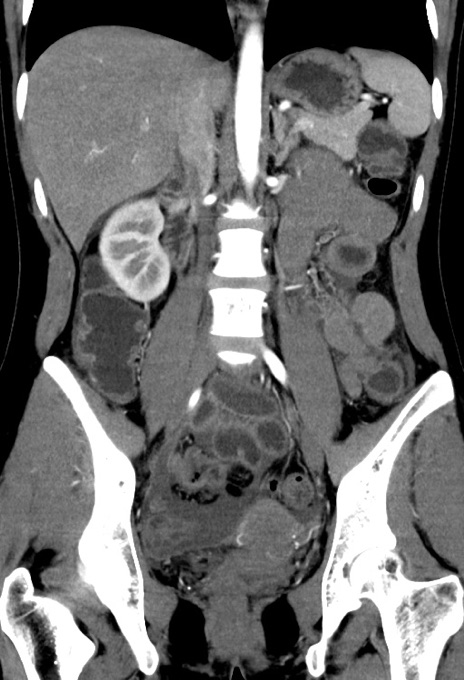

【症例】20歳代女性

【主訴】嘔吐、下腹部痛

【現病歴】昨日夕食後に嘔吐し下腹部痛が出現。本日になっても嘔吐持続し改善しないため来院。

【身体所見】意識清明、BT 37.2℃、BP 108/67mmHg、腹部:平坦、やや硬、下腹部正中から右にかけて圧痛あり、反跳痛軽度あり、tapping pain(+)。

【データ】WBC 13600、CRP 14.94